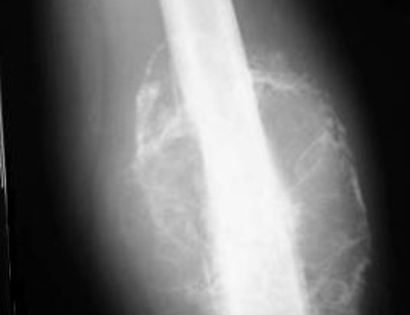

Curettage and Midas Rex Burr

Curettage